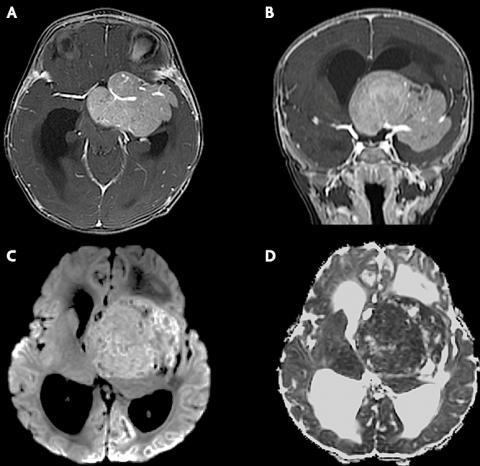

【二周:T1WI(A)和T2WI(B)轴位磁共振图像显示肿块为T1等信号(相对于皮质)和T2低信号。肿块导致梗阻性脑积水,导致中度侧脑室扩大和室周水肿。】

【三周:轴向(A)和冠状(B)对比增强T1WI显示包裹左侧大脑中动脉的较大鞍上肿块的增强。】